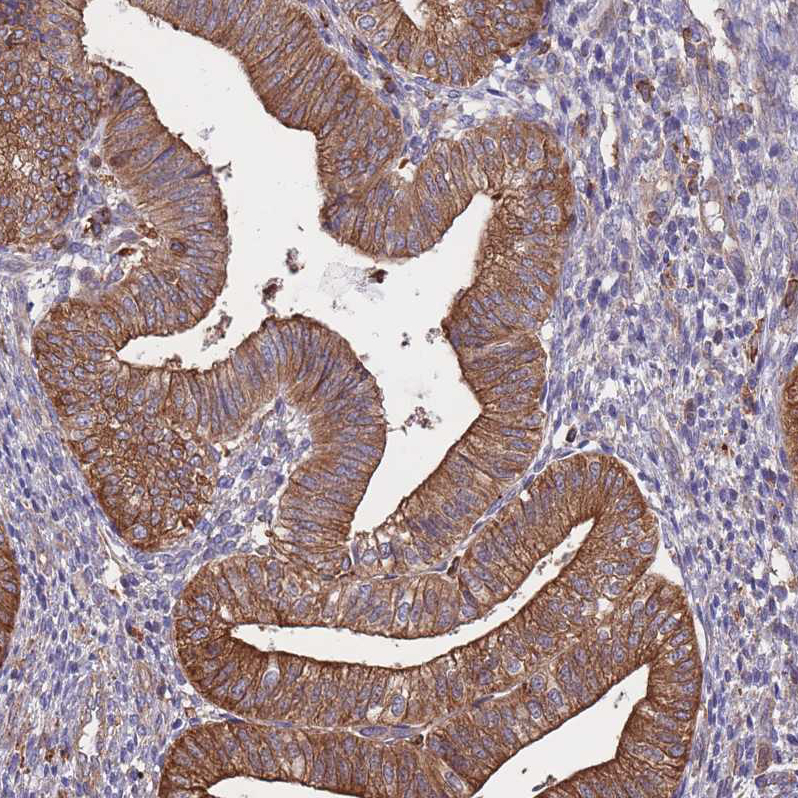

Immunohistochemistry analysis in human endometrium and liver tissues using HPA050317 antibody. Corresponding LRRN4CL RNA-seq data are presented for the same tissues.